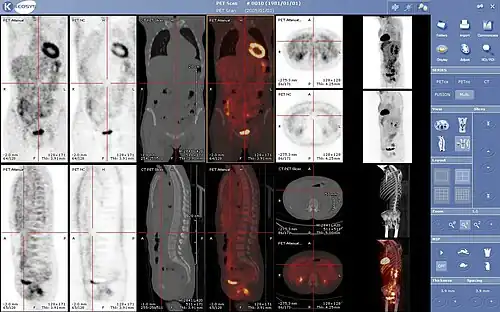

- Normal whole body PET/CT scan with FDG-18. The whole body PET/CT scan is commonly used in the detection, staging and follow-up of various cancers.

- Abnormal whole body PET/CT scan with multiple metastases from a cancer. The whole body PET/CT scan has become an important tool in the evaluation of cancer.